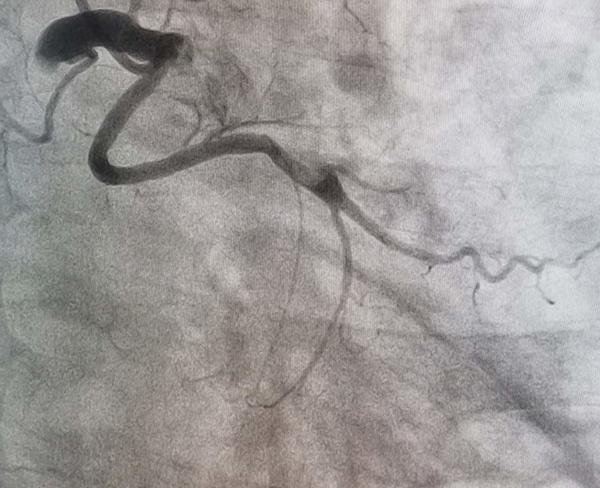

The coronary angiography revealed left system LAD and ramus without lesions, RCA no lesions, and anomalous origin of the circumflex coronary artery from the proximal segment of the RCA without lesions. (Figure 2 and Video 1).

Figure 2.